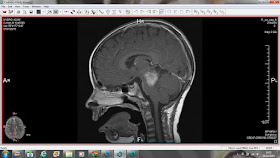

13.05.2015 dzień rezonansu...

wzrost w stronę wzgórza, możdżku i mostu pnia mózgu, widoczny ucisk na prawą półkulę. Guz ma ponad 2 cm...

13.05.2015